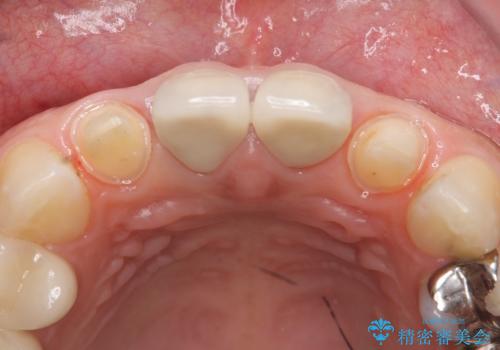

- 上顎の前から2番目の歯の古い樹脂をセラミックにしたいといらっしゃった方の症例です。

古い樹脂を除去後、オールセラミッククラウンによる補綴を行いました。